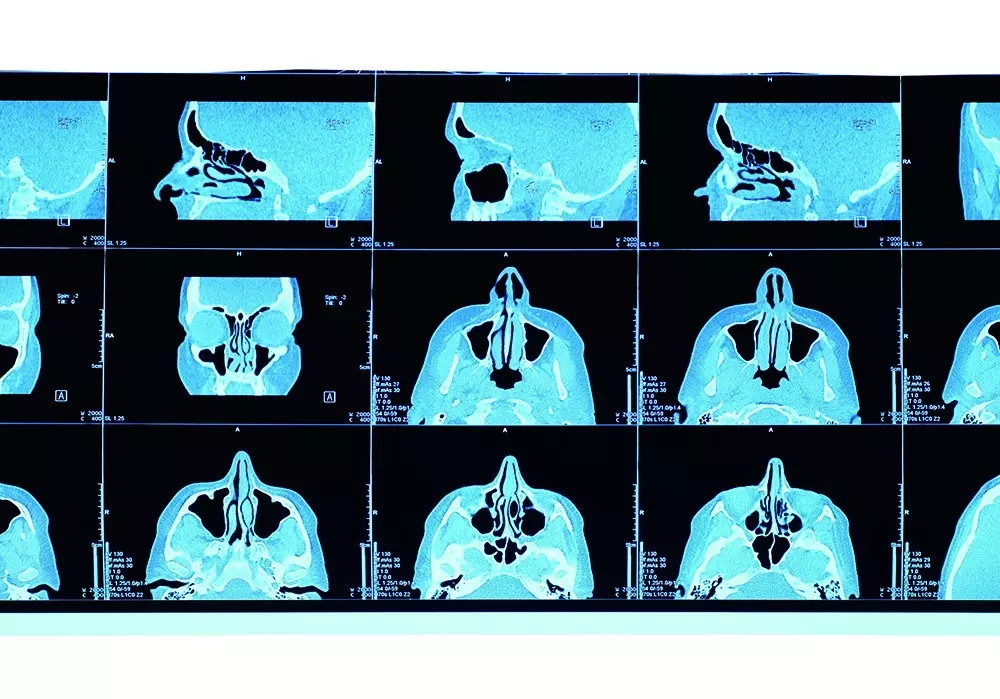

Laser diodowy w ortodoncji znajduje zastosowanie m.in. podczas wprowadzania zatrzymanego kła do łuku zębowego, redukcji bólu po założeniu aparatu ortodontycznego oraz korekty przerostu dziąseł na skutek leczenia aparatem stałym. Dr n. med. Rafał Flieger i dr n. med. Jacek Matys opisują w swoim artykule ww. przypadki, odwołując się do konkretnych przykładów leczenia.